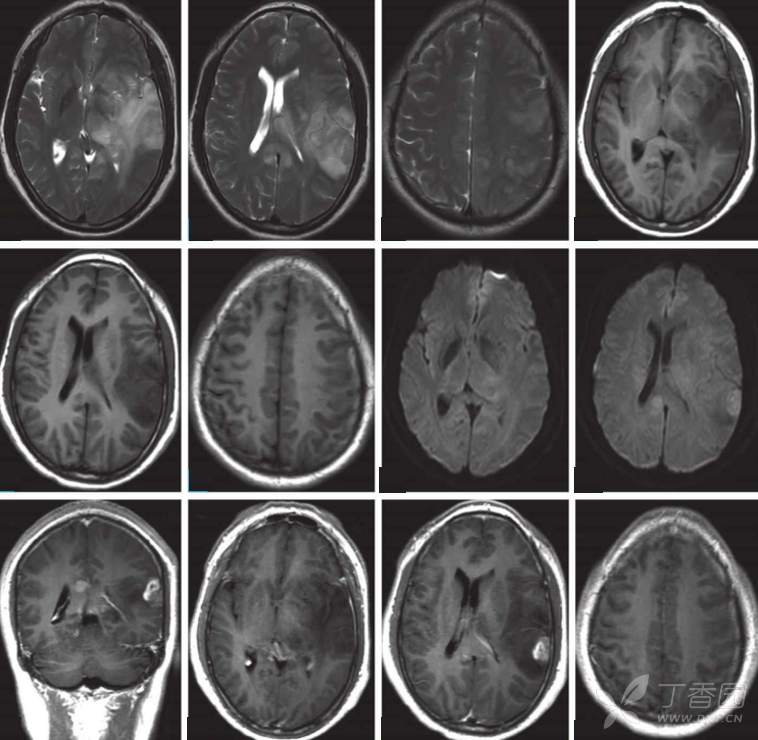

依次为:轴位T2WI; T1WI; 轴位DWI;冠状位T1WI增强;轴位T1WI增强